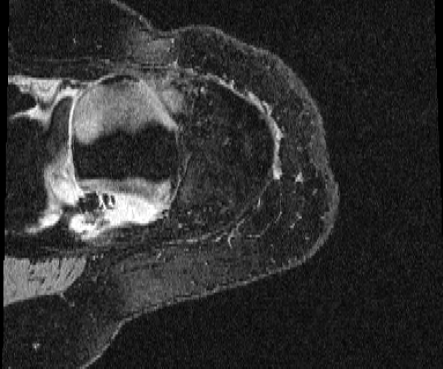

COPDGene / Dirlab lung CT. We follow the data selection and preprocessing of [23]. We train on 999 inhale/exhale pairs from COPDGene [18], masked with lung segmentations, clipped to [-1000, 0] Hounsfield units, and scaled to (0, 1). We evaluate landmark error (MTRE) on the ten inhale/exhale pairs of the Dirlab challenge dataset [4]333https://tinyurl.com/msk56ss5.

| Moving Image | Warped Image | Fixed Image | Moving Image | Warped Image | Fixed Image |